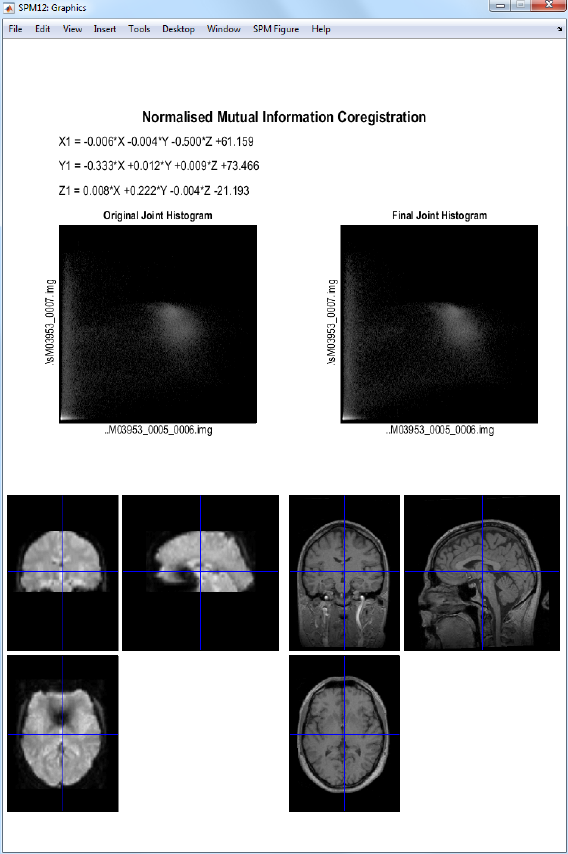

30.2.2 Coregistration ..................................223

31.1.4 Coregistration ..................................248

31.1.5 Segmentation ...................................248